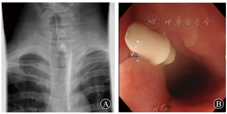

例2 患者女,60岁,因"恶心、呕吐1年"于2018年7月6日入院。2016年9月患者因发现贲门癌行腹腔镜下近段胃切除术和食管残胃空肠双通道吻合术。术后半年,患者恶心、呕吐症状逐渐加重,行胃镜检查提示盲端近吻合口处可见一瘘口(图4A),上消化道造影提示吻合口空肠瘘(图4B)。于2018年7月10日予内镜下OverStitch缝合术闭合瘘口,手术过程顺利,术中使用1根缝合线,缝合6针,总手术时间约为75 min。术后患者症状明显缓解,于2018年7月13日出院。术后3个月复查胃镜和上消化道造影均提示瘘口已完全闭合(图5)。